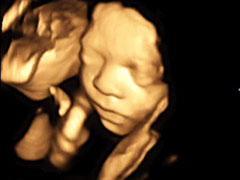

Hier zeigt ein kleiner Film einen 4D-Ultraschall

Klicken, um den Film zu sehen

Baby 4D UltraschallBaby 4D UltraschallBaby 4D UltraschallBaby 4D UltraschallBaby 4D UltraschallBaby 4D UltraschallBaby 4D UltraschallBaby 4D UltraschallBaby 4D UltraschallBaby 4D UltraschallBaby 4D UltraschallBaby 4D Ultraschall4 - 6<>